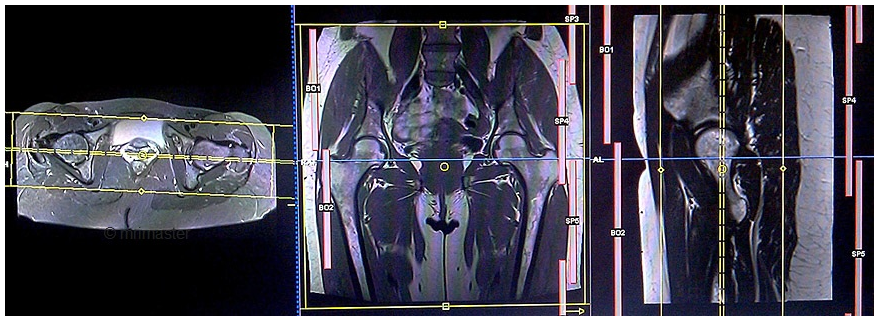

2. Chụp cộng hưởng từ khớp háng

Khớp háng là khớp có cấu trúc và chức năng phức tạp, bệnh lý liên quan khớp bao gồm chấn thương, tổn thương xương, hoại tử khớp, viêm khớp, thoái hóa khớp, u... Có nhiều khảo sát hình ảnh cho các bệnh lý khớp háng. X quang thường là chỉ định đầu tiên. Chụp cắt lớp vi tính có giá trị đánh giá chi tiết cấu trúc xương, vỏ xương, nhưng chụp cộng hưởng từ khớp háng có vai trò đặc biệt quan trọng trong đánh giá các cấu trúc phần mềm cấu tạo nên khớp háng như: bao khớp, sụn khớp, các cơ tham gia vào vận động khớp háng, tủy xương....